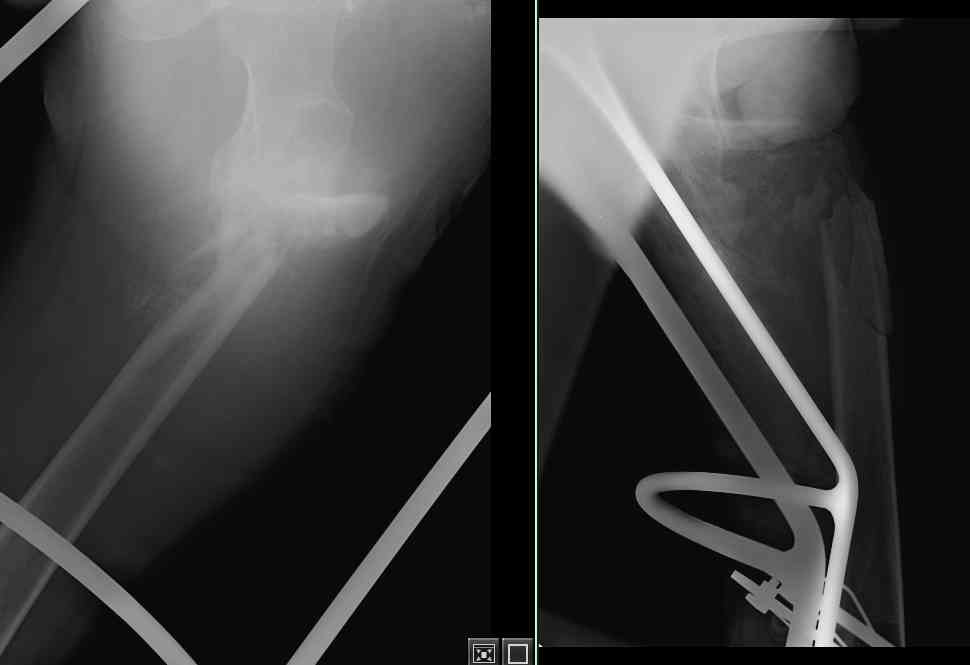

[Ortho] Неправильно консолидирующийся перелом бедра

Произведена секвестрэктомия, остеотомия костной мозоли(кстати говоря мозоль оказалась довольно таки приличной) Рана  ушита нагрухо. Наложено ДСВ за мышелки бедра. Рана зажила первичным натяжением. Пациенту наложен коксит, готовится на выписку.